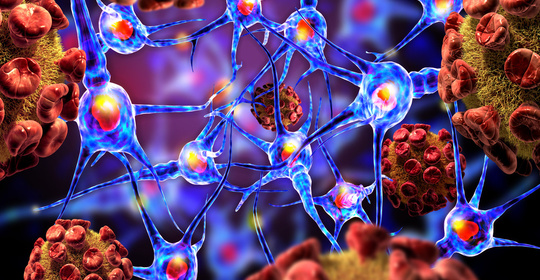

超雄現象對男性健康的影響,這些症狀需警惕

雄激素過多:維護男性荷爾蒙平衡的小秘訣!

雄激素過少的影響及調理方法,男性健康的小撇步!

錐體外系統損害:男性健康問題,聚焦外系疾病與康復策略

血睪酮降低:男性健康問題及潛在治療方法